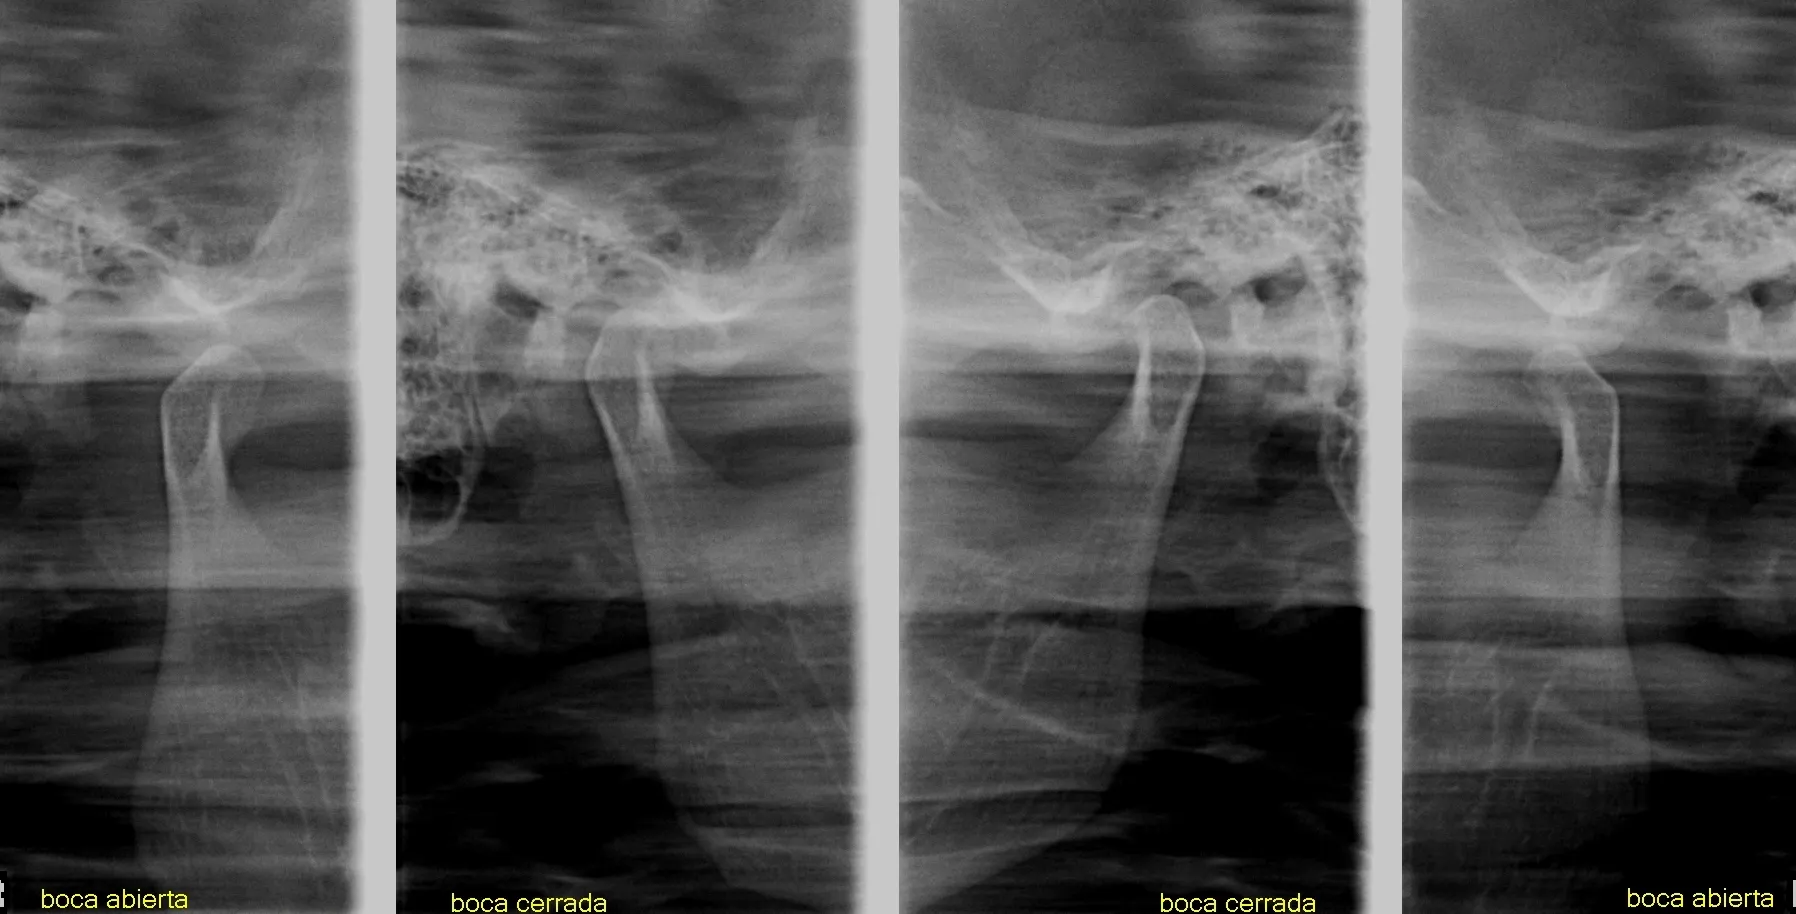

Las radiografías extraorales permiten obtener imágenes completas de los maxilares, la articulación temporomandibular (ATM) y las estructuras faciales sin colocar el sensor dentro de la boca.

Realizamos estudios como radiografía panorámica, cefalométrica, de senos paranasales y de ATM, esenciales para tratamientos de ortodoncia, cirugía y diagnóstico integral.